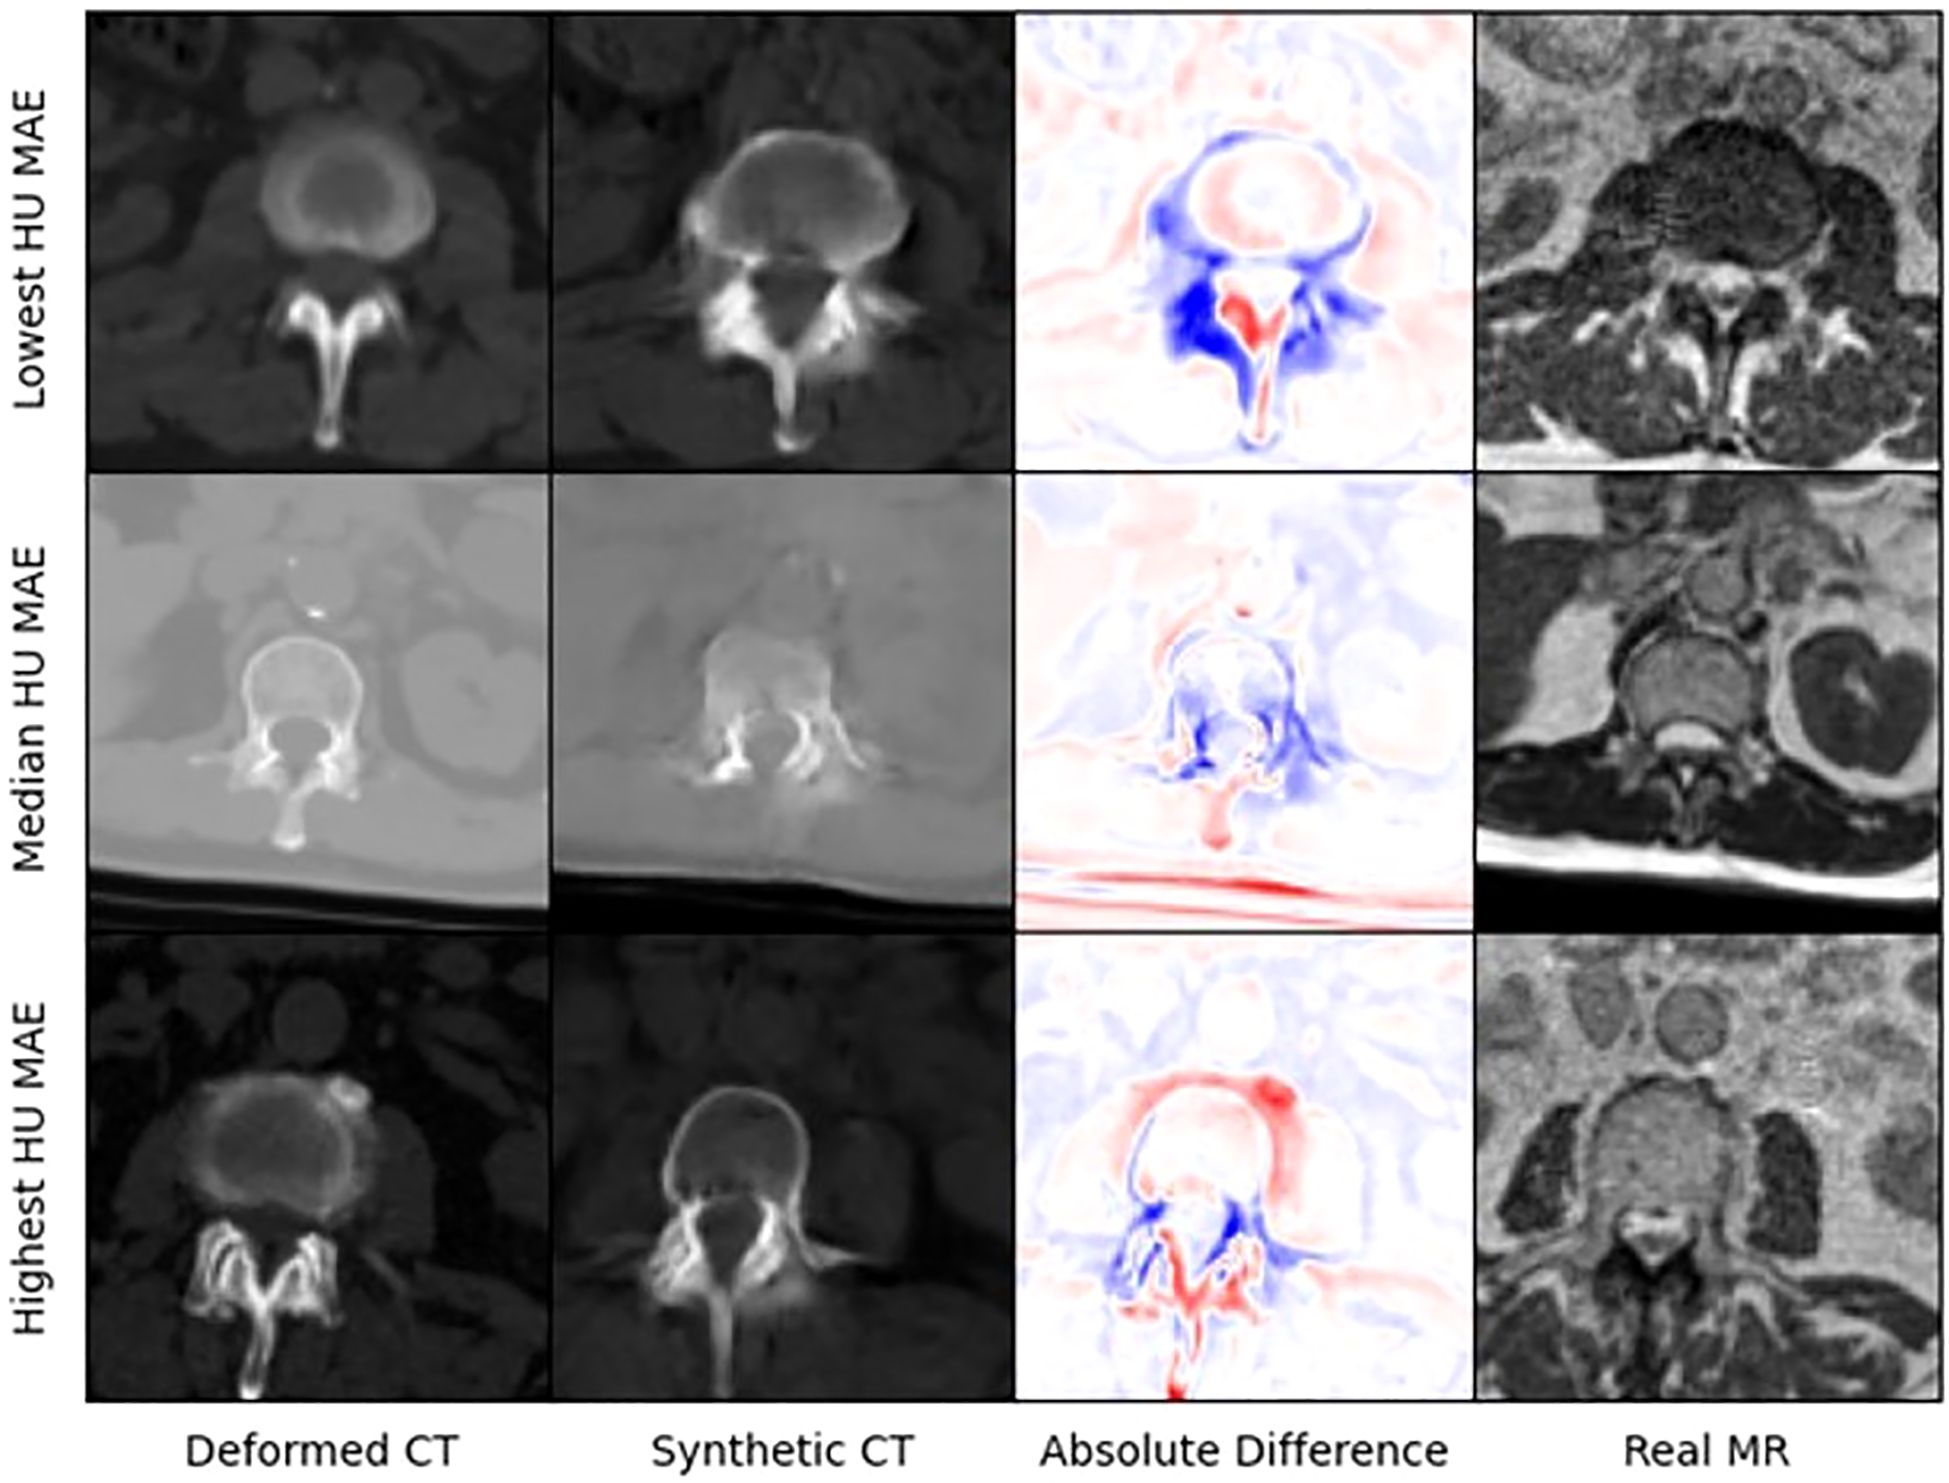

Figure 4 presents selected images from the scans with the lowest, median, and highest MAE (HU) from our test set. Figure 5 shows zoomed in panel of spinal region of interest. We compare sCT spinal reconstruction on lowest, median, and highest HU MAE patients. As is evident in all three examples, our model struggled to properly predict skin, bone, and limbs outside of the torso region (arms). Difficulty predicting bone is consistent with prior works (20, 21). Additionally, we view differences between the sCT and dCT with regards to air bubbles. For example, in the median HU images, we observe that our synthetic CT images correctly include air bubbles present in MR, whereas the deformed CTs do not include said bubbles. However, from a qualitative perspective, our sCT reconstructions are minimally different from their deformed CT counterparts.

Figure 5. Zoomed in panel of spinal region of interest. We compare sCT spinal reconstruction on lowest, median, and highest HU MAE patients.

Our treatment dose comparison also supports an MRI-only RT workflow. Our 0.45 Gy, 0.47 Gy, and 0.46 Gy average difference in dose delivered to PTV for 85%, 90%, and 95% of the volume indicates that sCTs have minimal effects on dose delivered. Additionally, NCC comparisons in Table 4 indicate that synthetic CTs capture an equivalent to better representation of the MR scans taken during treatment. Thus, we can extrapolate that synthetic CT scans may present a more precise image to calculate RT dose with. Exemplary of this claim are the air bubbles in the median MAE frame of Figure 3. From a visual comparison to the real MR, we can see that the synthetic CT better models air bubbles. Thus, the synthetic CT is likely a better representation to use when performing dose calculations. Another observed benefit of synthetic CTs is the elimination of artifacts compared to deformable CTs. Given that sCT generation is wholly dependent on the MR image fed into the model, if this MR image has no artifacts the resulting sCT will be artifact-free as well.

Some limitations of our approach include limited frame to frame cohesion on the axial plane. We observed that although primary image structures and features remained fixed, there were some frame-to-frame shifts in axial position along the extremities of each scan. These shifts may have occurred because the CycleGAN architecture trains on a single image at a time as opposed to a whole volume. Therefore, the model has more difficulty learning frame to frame continuance. Another observed limitation to our method is that our model has difficulty predicting HU values for high-intensity regions. For example, in Figure 4, we see that for all 3 image examples our model had difficulty reconstructing and predicting spine intensity values. We believe that this is due to the intrinsic distribution of HU values. Bone HU values are typically above 700, whereas all other tissue HU values fall between -100 and 300 HU. Thus, distribution imbalances may have led to difficulties predicting HU values for high-intensity regions. Finally, we believe that some distribution-matching losses may have caused anomalously shaped structures in certain already hard-to-predict regions such as the spine. For example, the spinal structure of all three sCTs in Figure 4 differs from their dCT ground truths. Given their relative similarity to each other, we believe that these differences may correspond to hallucinated features caused by distribution-matching losses, a phenomenon previously observed in Cycle-GAN based image translation (29).